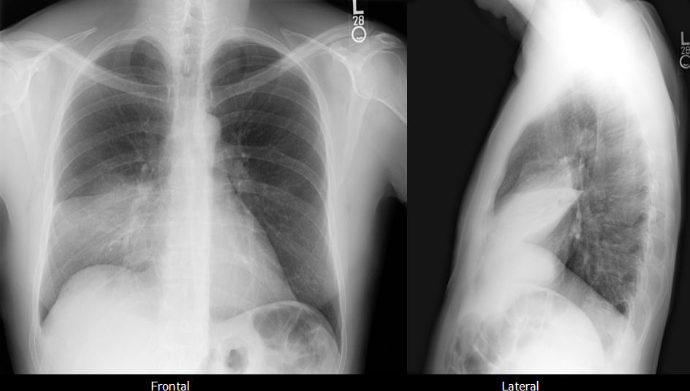

Collapse consolidation of the middle lobe. Posteroanterior and lateral views. The collapsed lobe is most obvious on the lateral view. Note the silhouette sign obliterating the lower right heart border.

Lateral: Arch of heart - oblique/Horizontal fissures